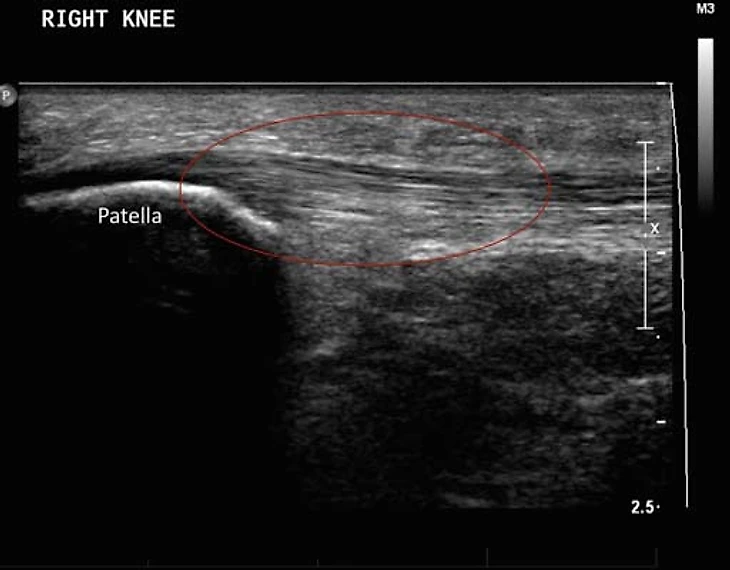

Вот, как это примерно выглядело в случае Маслова.

Как мы видим, УЗИ позволяет точнее оценить степень изменений в сухожилии, особенно это касается неоваскуляризации. Плюс, это динамический метод, то есть мы можем попросить пациента двигать ногой, сокращать мышцы бедра и оценить, как на это реагирует сухожилие. В случае МРТ мы можем оценить лишь статичную картинку. Но и у МРТ есть свои плюсы — больший объем оцениваемых тканей; позволяет оценить еще и состояние сустава, куда ультразвуковой сигнал уже не добирается. Плюс, УЗИ хороший метод только при оценке поверхностно лежащих тканей. В случае тендинопатии в других областях МРТ может оказаться точнее и более предпочтительным методом.